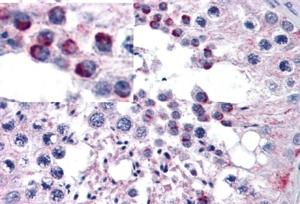

APR11951G (5 μg/ml) staining of paraffin embedded Human Testis. Steamed antigen retrieval with citrate buffer pH 6, AP-staining. |